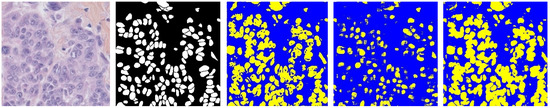

Breast Cancer Histopathological Images Segmentation Using Deep Learning

3. Methodology

3.2. Segmentation Based on Improved U-Net

4. Results and Discussion